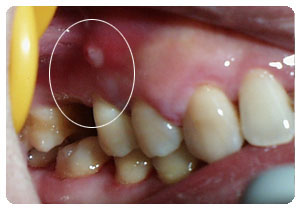

(2)慢性根尖周脓肿:多无自觉症状,在患牙的根尖区黏膜处可有瘘管,瘘管口处常有肉芽组织增生,可有脓液自瘘管排出,因有瘘管引流,不易转为急性炎症。

(3)根尖囊肿:多无自觉症状,牙齿变色,牙片可显示根尖部的囊肿,若囊肿增大,迫使周围骨质吸收,在患牙根尖部黏膜多呈半圆形隆起,有乒乓球感。